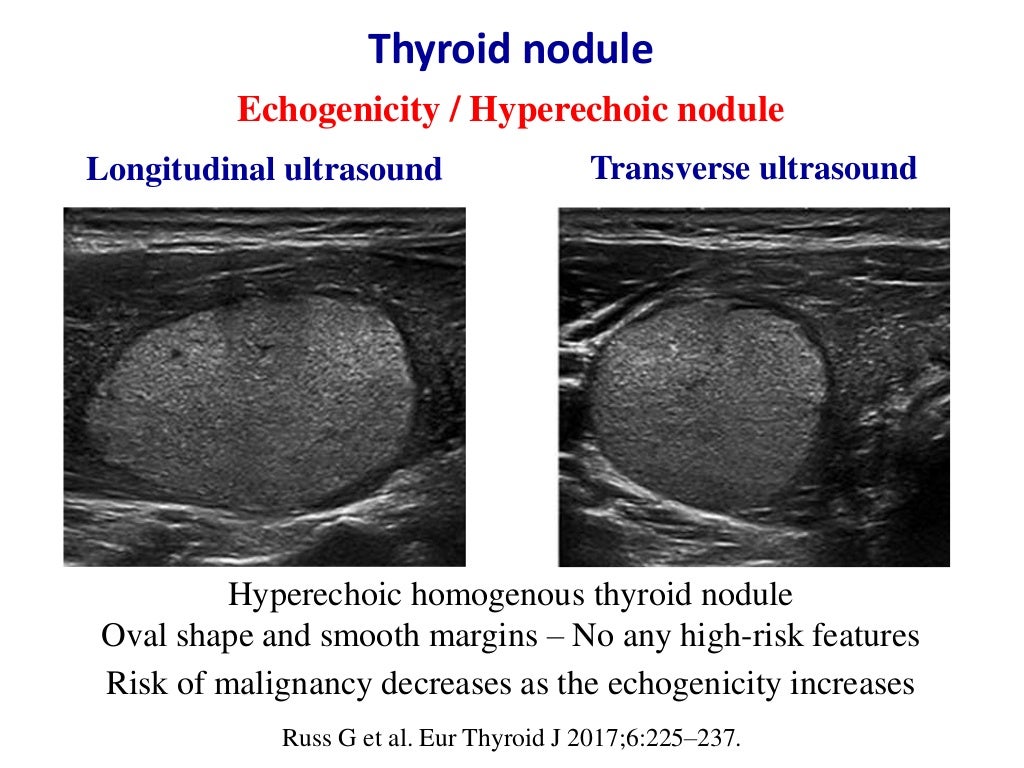

Thyroid Ultrasound

Thyroid Ultrasound

Inspissated Colloid In A Thyroid Nodule Radiology Case

Thyroid Nodule With Taller Than Wide Dimensions Download Scientific